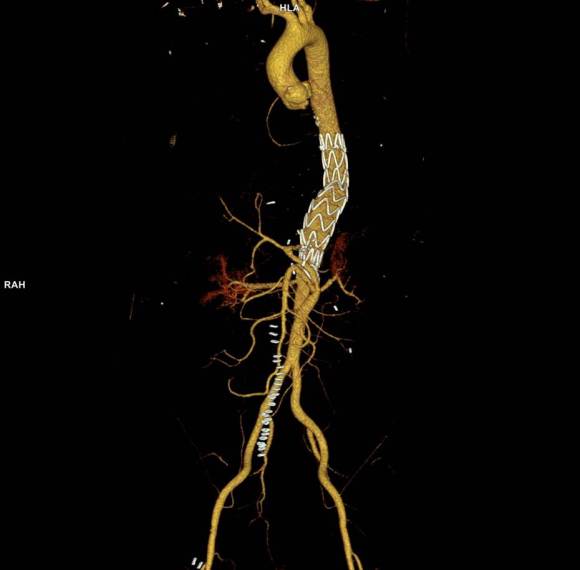

Open repair, usually the most expeditious option, was made challenging by the right hemothorax, making a left thoracotomy hazardous if the lung had to be deflated. Cardiopulmonary bypass would have to be arranged for, and that adds a metabolic hit that greatly raises the stakes. Of the endovascular solutions, the only viable option was TEVAR to exclude the rupture and debranching of the celiac axis and superior mesenteric artery. To those who would advocate for parallel grafts, there was no room in the normal 20mm diameter aorta. And branch systems for rupture are some time in the future. Also, the patient was becoming hypotensive. So the planned operation was first TEVAR to stop the bleeding, and then open surgical debranching. A hybrid repair.

The smallest stent graft we have is a 21mm graft, but it would not be suitable for this aorta. In practice, the normal aorta is quite elastic and will dilate much more than what is captured on a CTA. The next size we have is 28mm graft and I chose this to exclude the rupture, which was done percutaneously.

The bypasses were sent from the infrarenal aorta to the common hepatic artery and the SMA close to its origin, and the origins of the celiac axis and SMA were clipped. The bypasses were then done with a 10x8mm bifurcate Dacron graft originally for axillofemoral bypassing. It had spiral rings which I removed at the anastomosis and this resulted in a kink at the closer bypass. Usually, I loop this for iliomesenteric bypass but there was not enough distance from the infrarenal aorta. I have to add a little trick I modified from my pediatric surgery experience as a resident -a Heinecke-Mikulwicz graftoplasty: